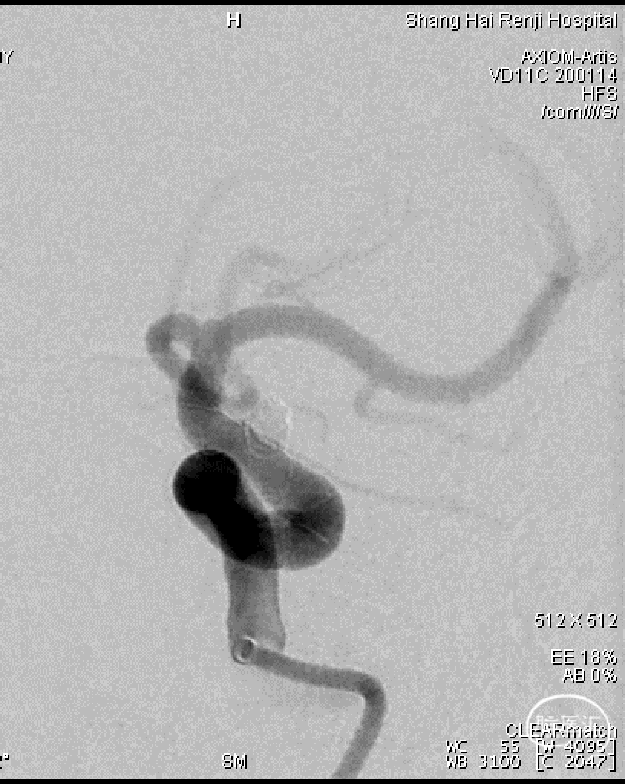

术后影像

图7. a,b:术后即刻正侧位造影显示动脉瘤已完全闭塞(Raymond I级)。

患者术后3天出院,mRS 0分。